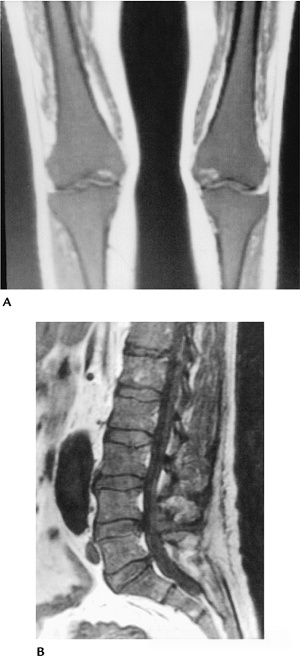

80390c30023905a3a790841455d25218.png

图-11骨髓纤维化。(A)胸部X光片显示骨密度增加和明显脾肿大。(B)骨盆X光片显示散在的骨硬化。腰椎前后位(C)和侧位(D)X光片显示骨密度增加。

908f8e2204e85c218c67070fbae696ae.png

图-12骨髓纤维化。股骨的T1像显示低信号度,除了远端。